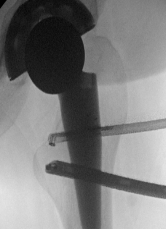

Use image intensifer to triangulate to lesser tuberosity

Psoas tendon Diathermy release Cleared lesser tuberosity